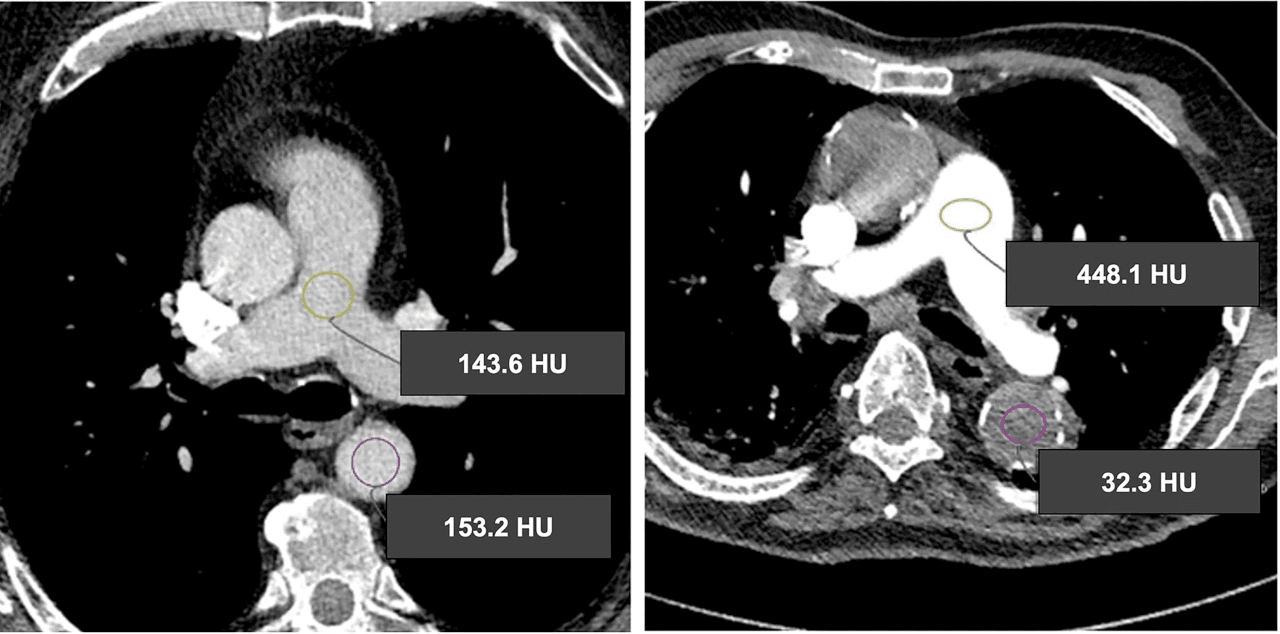

For more than a decade, Synapse Medical has supplied ulrich medical CT and MR contrast injectors. But while ulrich remains a cornerstone of its portfolio, Synapse has entered a period of growth, bringing more innovative solutions to diagnostic imaging professionals. Over the past year, it has partnered with several new suppliers whose products address key […]